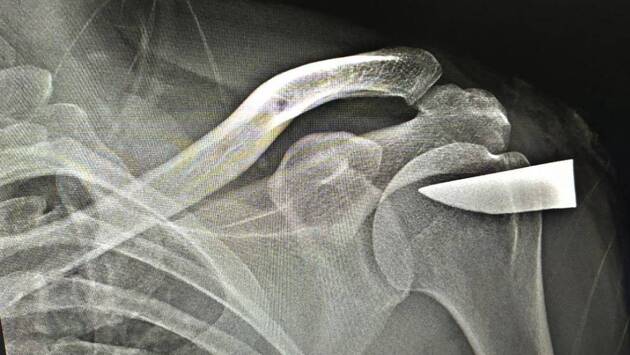

Кусок клинка в плече

40-летний мужчина пришел к врачам можайской больницы с жалобой на боль в плече. При этом он не смог вспомнить, когда и как получил злополучную травму.

Результаты рентгена поразили врачей: причиной боли был шестисантиметровый осколок клинка. Посторонний предмет глубоко вошел в плечевую кость.

Хирурги удалили осколок и зашили рану. Шокированный пациент решил оставить «трофей» на память.